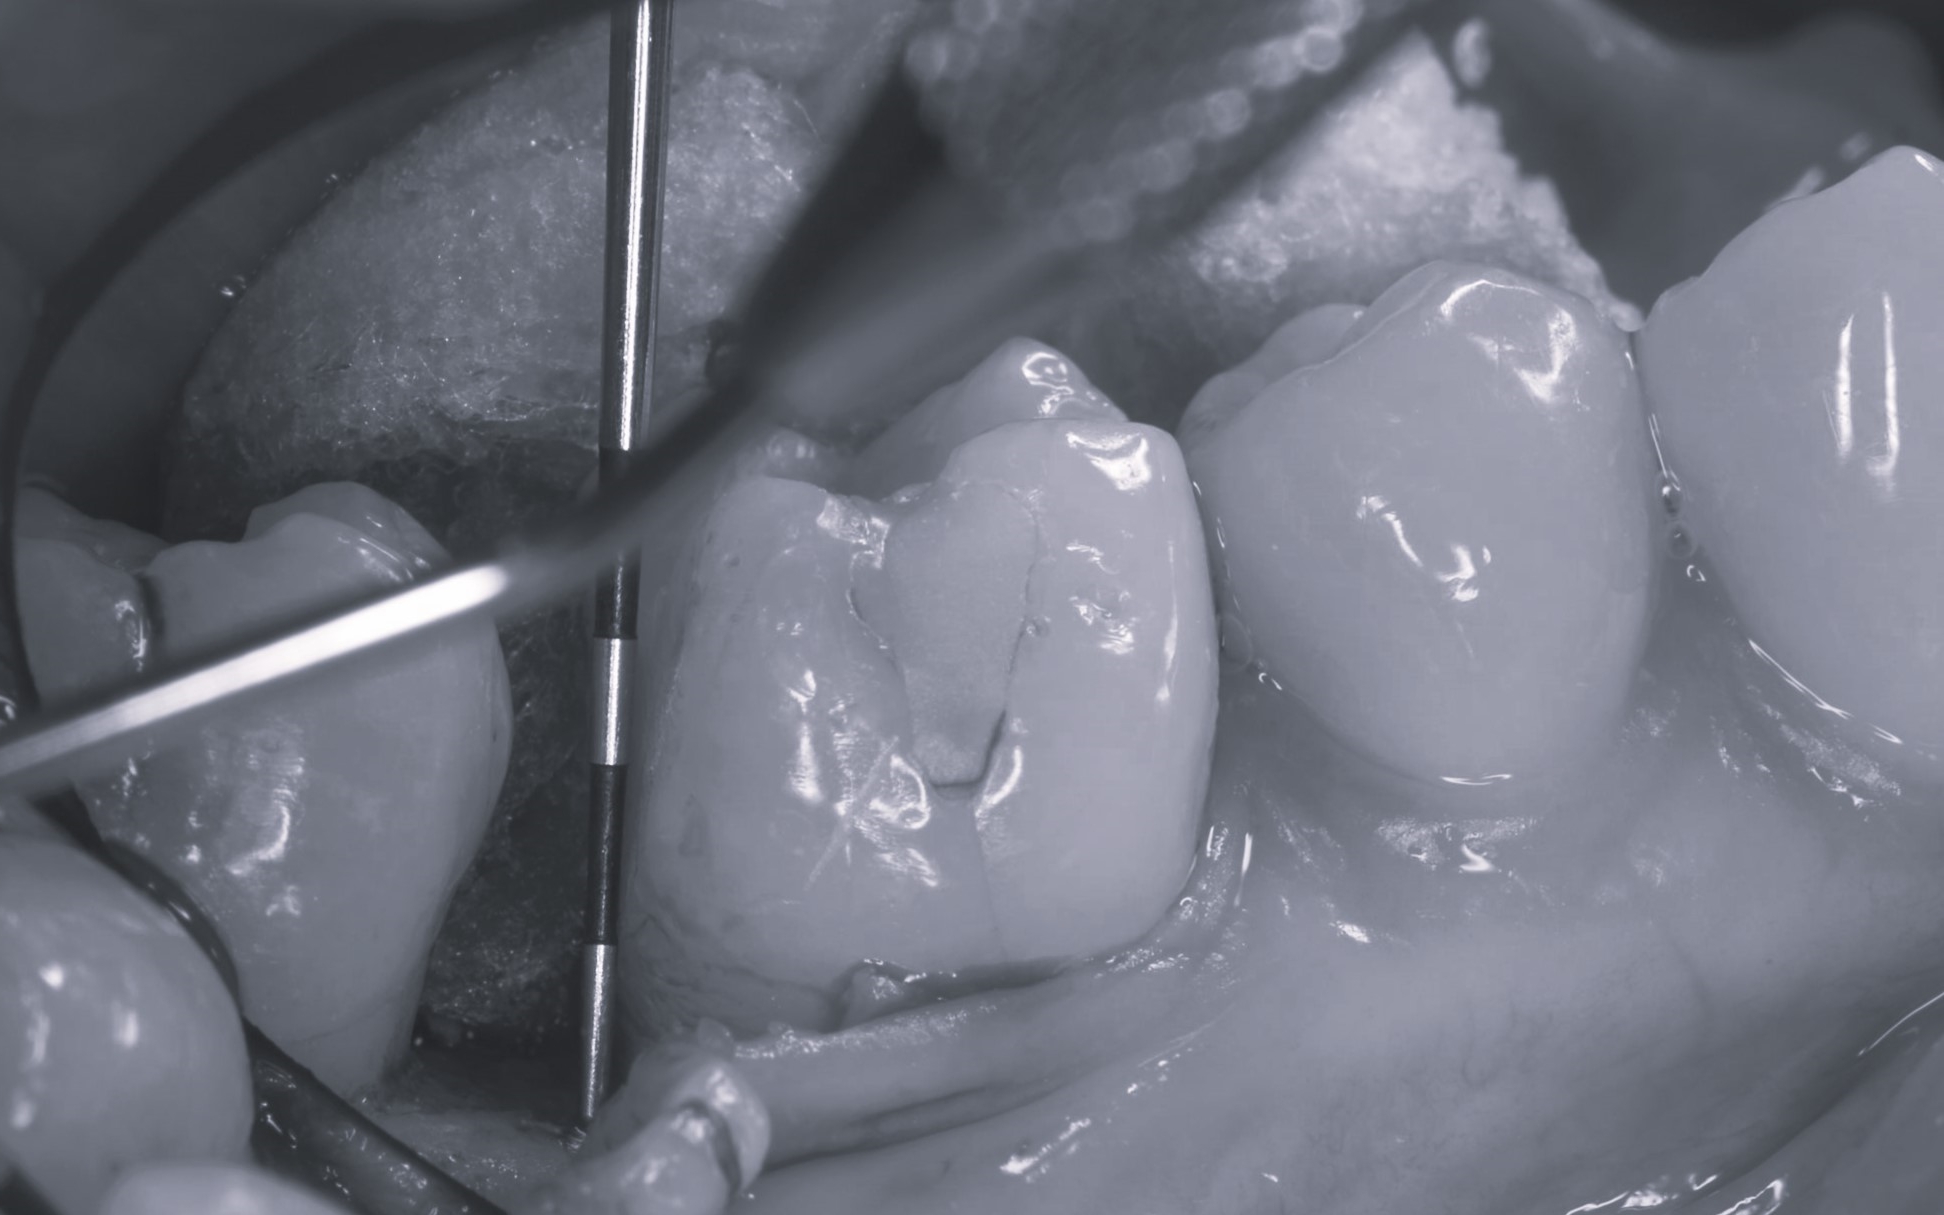

歯周外科手術を行いました。

精密根管治療を行いました。

精密な型取りを行いました。